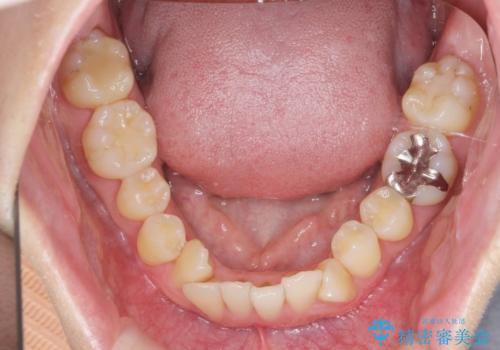

ねじれ・がたつきのある前歯を改善

- がたつき・すれ違い、ねじれのある前歯の見た目、噛み合わせの改善を希望され来院されました。

4本の小臼歯抜歯を避け、下顎前歯の1本抜歯の極力少ない抜歯本数で審美的な歯並びを得る治療計画としました。

すれ違いを治すのが得意な前歯部の部分ワイヤーを用いることで、治療期間を短縮することができました。